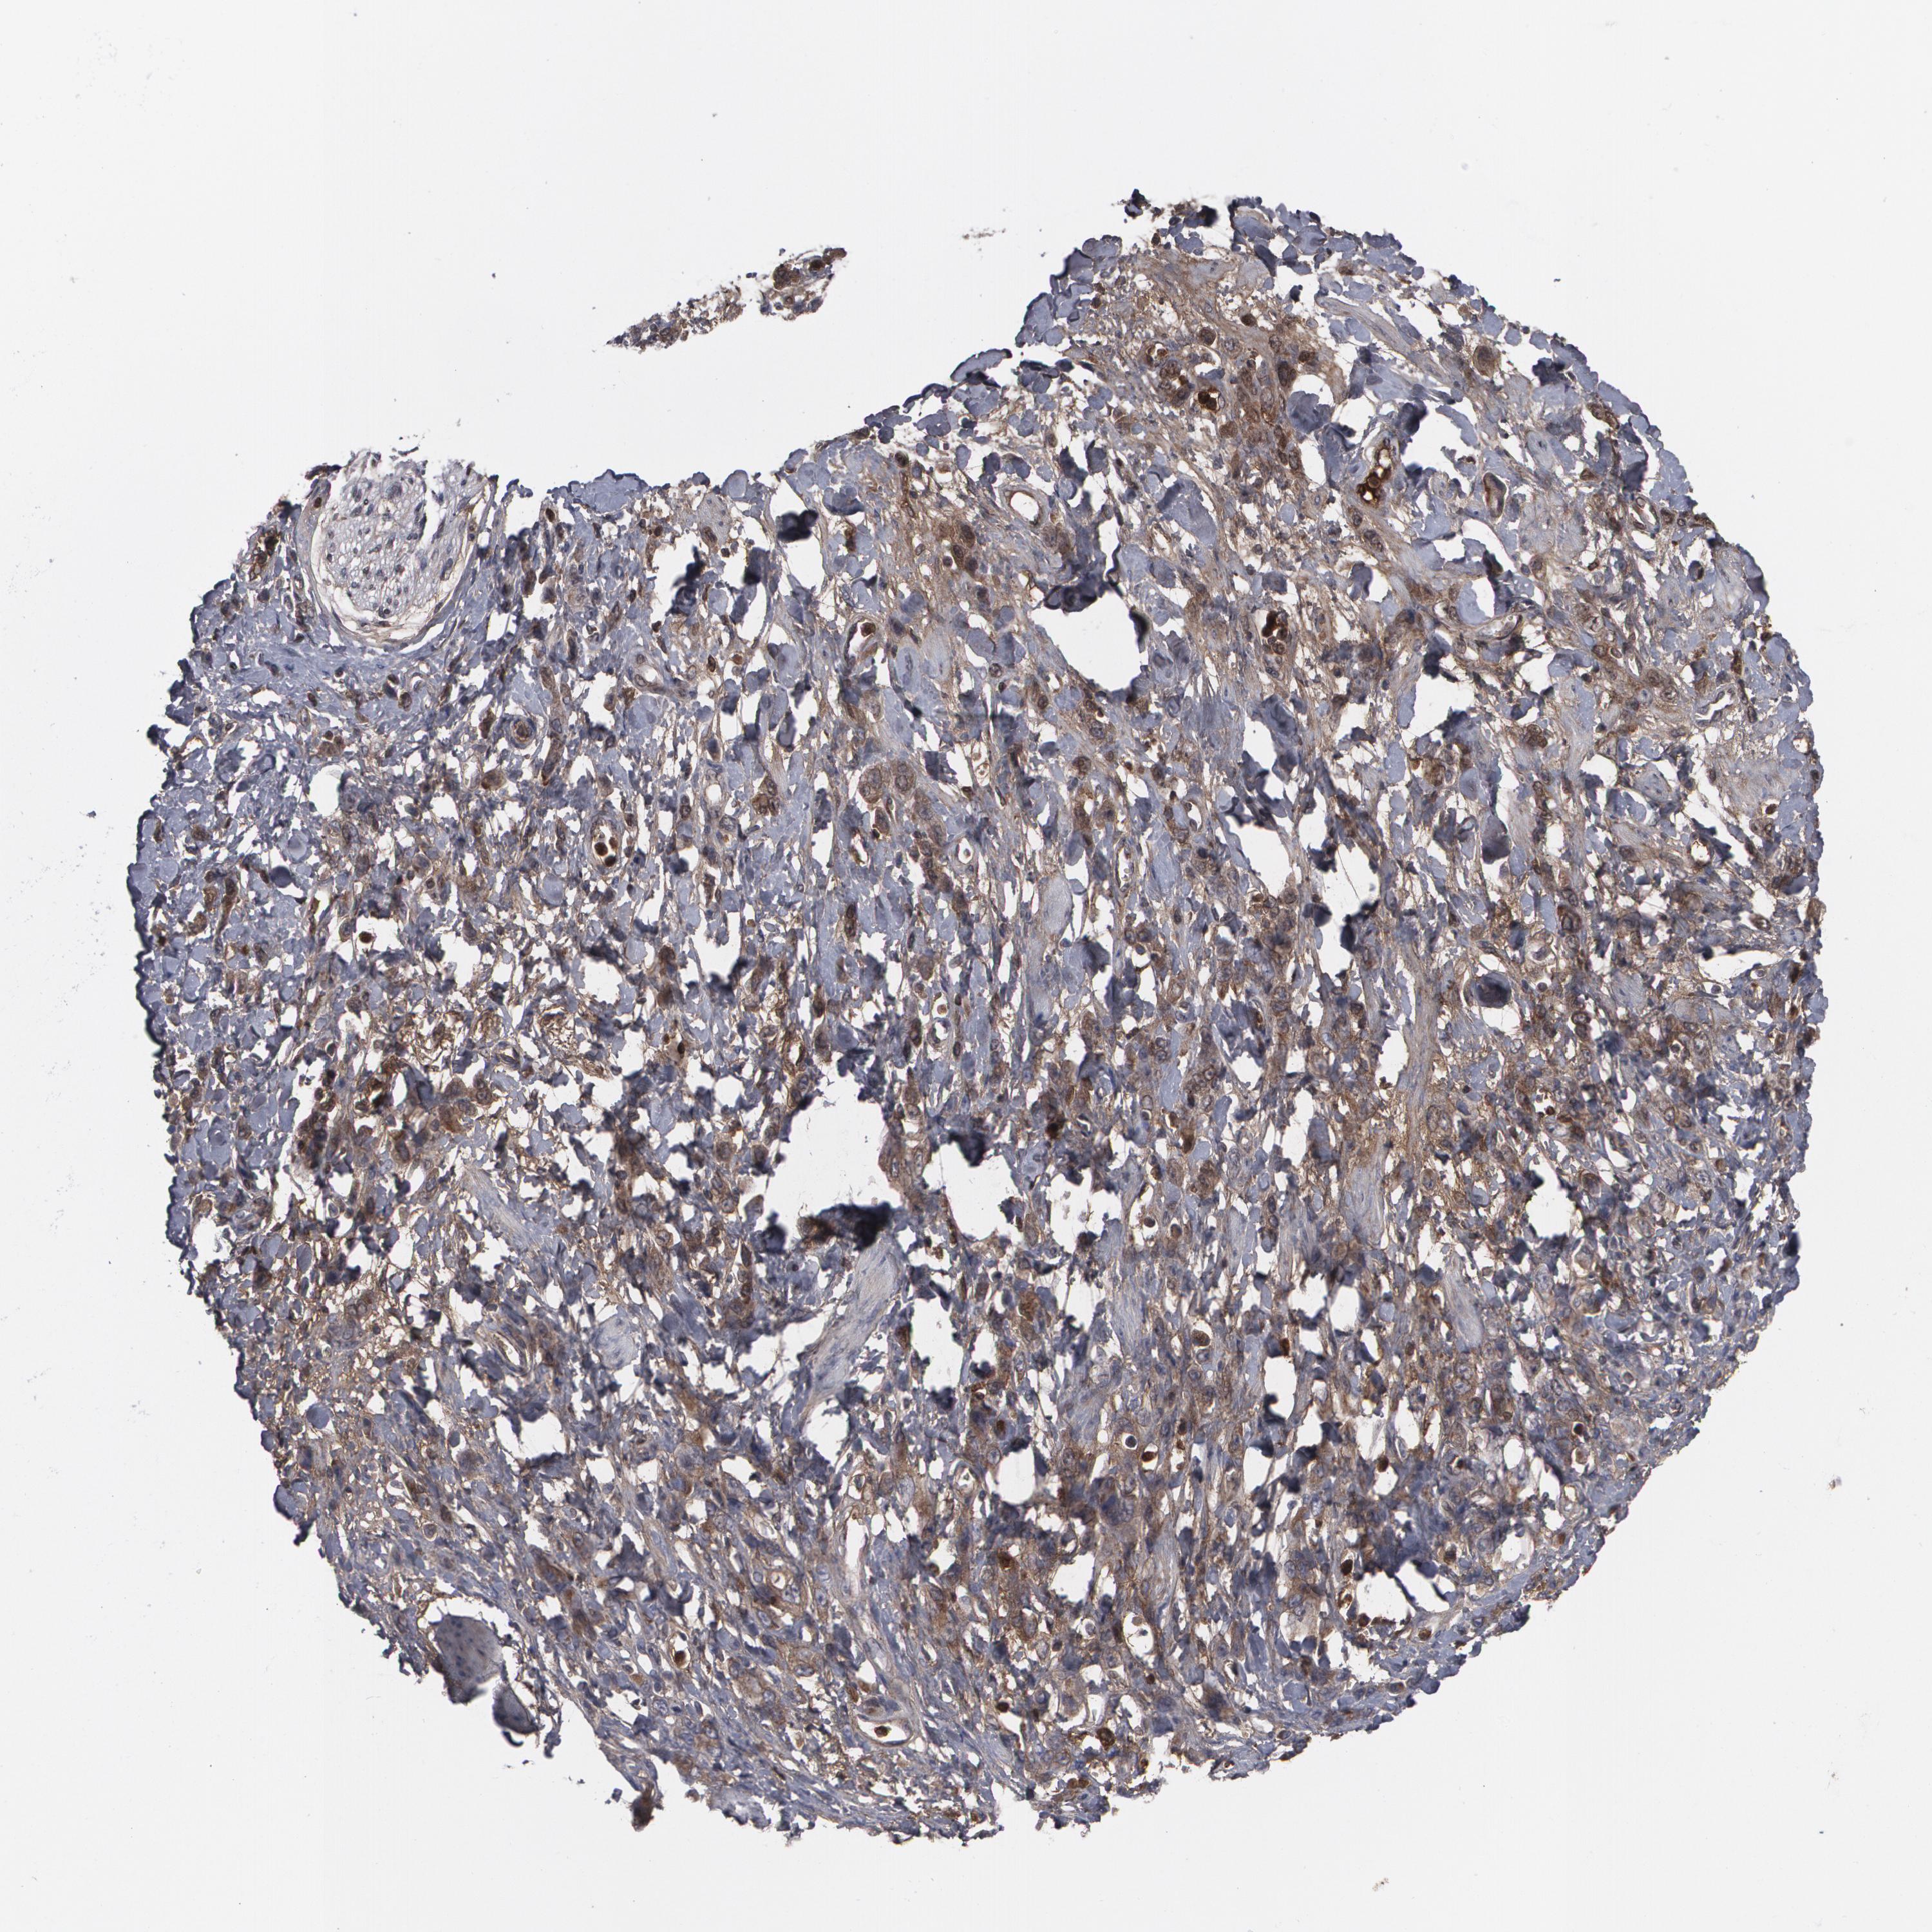

STOMACH CANCER - Protein expressioni

A mouse-over function shows sample information and annotation data. Click on an image to view it in a full screen mode. Samples can be filtered based on level of antibody staining by selecting one or several of the following categories: high, medium, low and not detected. The assay and annotation is described here.

Note that samples used for immunohistochemistry by the Human Protein Atlas do not correspond to samples in the TCGA dataset.

Antibody stainingi

Antibody staining in the annotated cell types in the current human tissue is reported as not detected, low, medium, or high, based on conventional immunohistochemistry profiling in selected tissues. This score is based on the combination of the staining intensity and fraction of stained cells.

Each image is clickable and will lead to virtual microscopy that enables deeper exploration of all samples and also displays staining intensity scores, fraction scores and subcellular localization as well as patient and tissue information for each sample.

Antibody HPA001888

Antibody HPA001889

Staining

High

Medium

Low

Not detected

Intensity

Strong

Moderate

Weak

Negative

Quantity

>75%

75%-25%

<25%

None

Location

Nuclear

Cytoplasmic/membranous

Cytoplasmic/membranous,nuclear

Adenocarcinoma, NOS

Adenocarcinoma, High grade